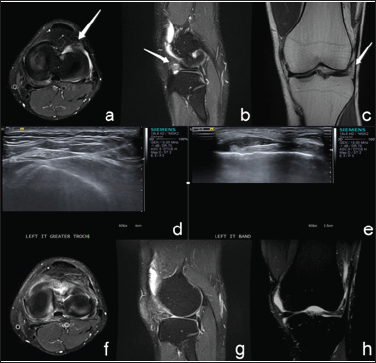

Meniscal cysts are an accumulation of synovial fluid within a sac present in the knee joint. The cysts may be separated into two types, parameniscal and intrameniscal. Both types may be present simultaneously [1]. Meniscal cysts represent about 1% to 10% of all meniscal pathology. They are caused by meniscal tears resulting in one-way valves that trap synovial fluid and are most commonly associated with horizontal cleavage tears of the lateral meniscus. Thought to be the result of age-related meniscal degeneration, meniscal cysts have now been diagnosed in adolescents and pediatric patients [2]. Intrameniscal cysts are found within the body or substance of the meniscus (Figure 1). Parameniscal cysts are classified as lateral or medial depending on from which meniscus the cyst protrudes. Meniscal cysts may be considered secondary indirect signs of meniscal tears [3]. Even when meniscal tears are not visualized, parameniscal cysts have a highly specific association with meniscal tears. Rutten et al. found coexisting meniscal tears in 85% of patients with parameniscal cysts [4]. Bergin et al. found parameniscal cysts in 7% of patients with meniscal tears [5].

The third layer contains the lateral joint capsule which attaches on the femoral and tibial articular boundaries. Bursae and soft tissues lie between the iliotibial band and lateral menisci. As such, parameniscal cysts extending from the lateral meniscus may cause friction with the iliotibial band, resulting in the hallmark inflammation and pain of ITBS (Figure 2).

Figure 2: As such, parameniscal cysts extending from the lateral meniscus may cause friction with the iliotibial band, resulting in the hallmark inflammation and pain of ITBS.

Meniscal cysts can be asymptomatic. However, symptomatic cysts usually present with symptoms typical of knee and/or meniscal injuries. Symptoms include pain, limited range of motion, swelling, tenderness along the joint line, and presence of a palpable mass along the joint line [1,2]. MRI is the modality of choice for detecting meniscal injuries [3]. In a study of 57 patients, researchers Crues et al. reported a sensitivity and specificity both of 92% for meniscal pathology on MRI as compared to arthroscopy [11]. On MRI, clinicians identify parameniscal cysts as fluid-intense lesions with clear connections to the adjacent meniscus [12]. Ultrasound is also useful for radiologic evaluation of meniscal cysts. In a study of 50 patients with a palpable mass, researchers Rutten et al reported a sensitivity and specificity of 97% and 86% respectively for meniscal cysts. (In the same study, researchers calculated a PPV of 94% and a NPV of 92%.) Clinicians identify parameniscal cysts as hypoechoic cysts in contact with the meniscus on ultrasound [4].

Treatment is based on the underlying pathology that led to cyst formation. Most commonly, meniscal tears require surgery to prevent recurrence of the meniscal cyst (Figure 3). The most common surgical technique is an arthroscopic partial meniscectomy with cyst decompression [1-2,14]. Reagan et al. concluded that 80% of their patients who underwent combined partial meniscectomy and open cyst excision, went on to report good-to-excellent results. Only 50% of patients who underwent partial meniscectomy alone reported good-to-excellent results [1]. In cases without associated meniscal tear, some clinicians utilize percutaneous decompression and debridement to optimize meniscal tissue preservation [1,2]. An alternative treatment option is ultrasound-guided percutaneous aspiration which is both simpler and less invasive. MacMahon et al. studied 18 patients who received ultrasound-guided percutaneous aspiration for lateral meniscal cysts [15]. Ten patients reported complete resolution of symptoms, two patients reported satisfactory sustained response with occasional pain, and the remaining six patients were pain-free between 1-8 weeks before pain returned.

Figure 6: Arthroscopy has a very high sensitivity and specificity as the gold standards for diagnosing injury.

MSKU can be used to quantitatively observe knee movement. MSKU is also a non-invasive, low-cost procedure, making it easier to obtain compared with other tests [24]. Arthroscopy has a very high sensitivity and specificity as the gold standards for diagnosing injury (Figure 6). However, it is both costly and invasive [25,26]. MSKU with high frequency probes can be used to clearly visualize the soft tissues around the knee and the peripheral edge of the menisci. MSKU can be used to easily guide needle placement for parameniscal cyst aspiration and injection for treatment of ITBS. With the advantages of easy operation, high accuracy, flexible use of in-plane and out-plane needle movement, ultrasound-guided treatment offers a strong alternative to invasive arthroscopic surgery. Although ultrasound-guided parameniscal cyst aspiration in patients with associated ITBS drug injection is promising, limitations exist. The operator needs to be skilled. He or she must guarantee the accuracy of the needle can and take care to avoid the common peroneal nerve.